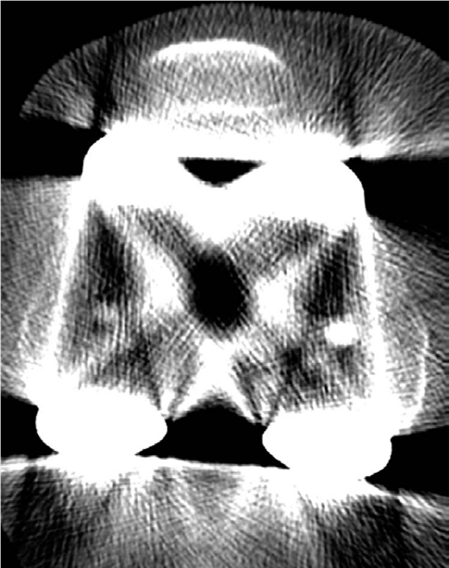

KNEE Structured oral examination question7: Revision knee replacement EXAMINER : Have a look at these images …